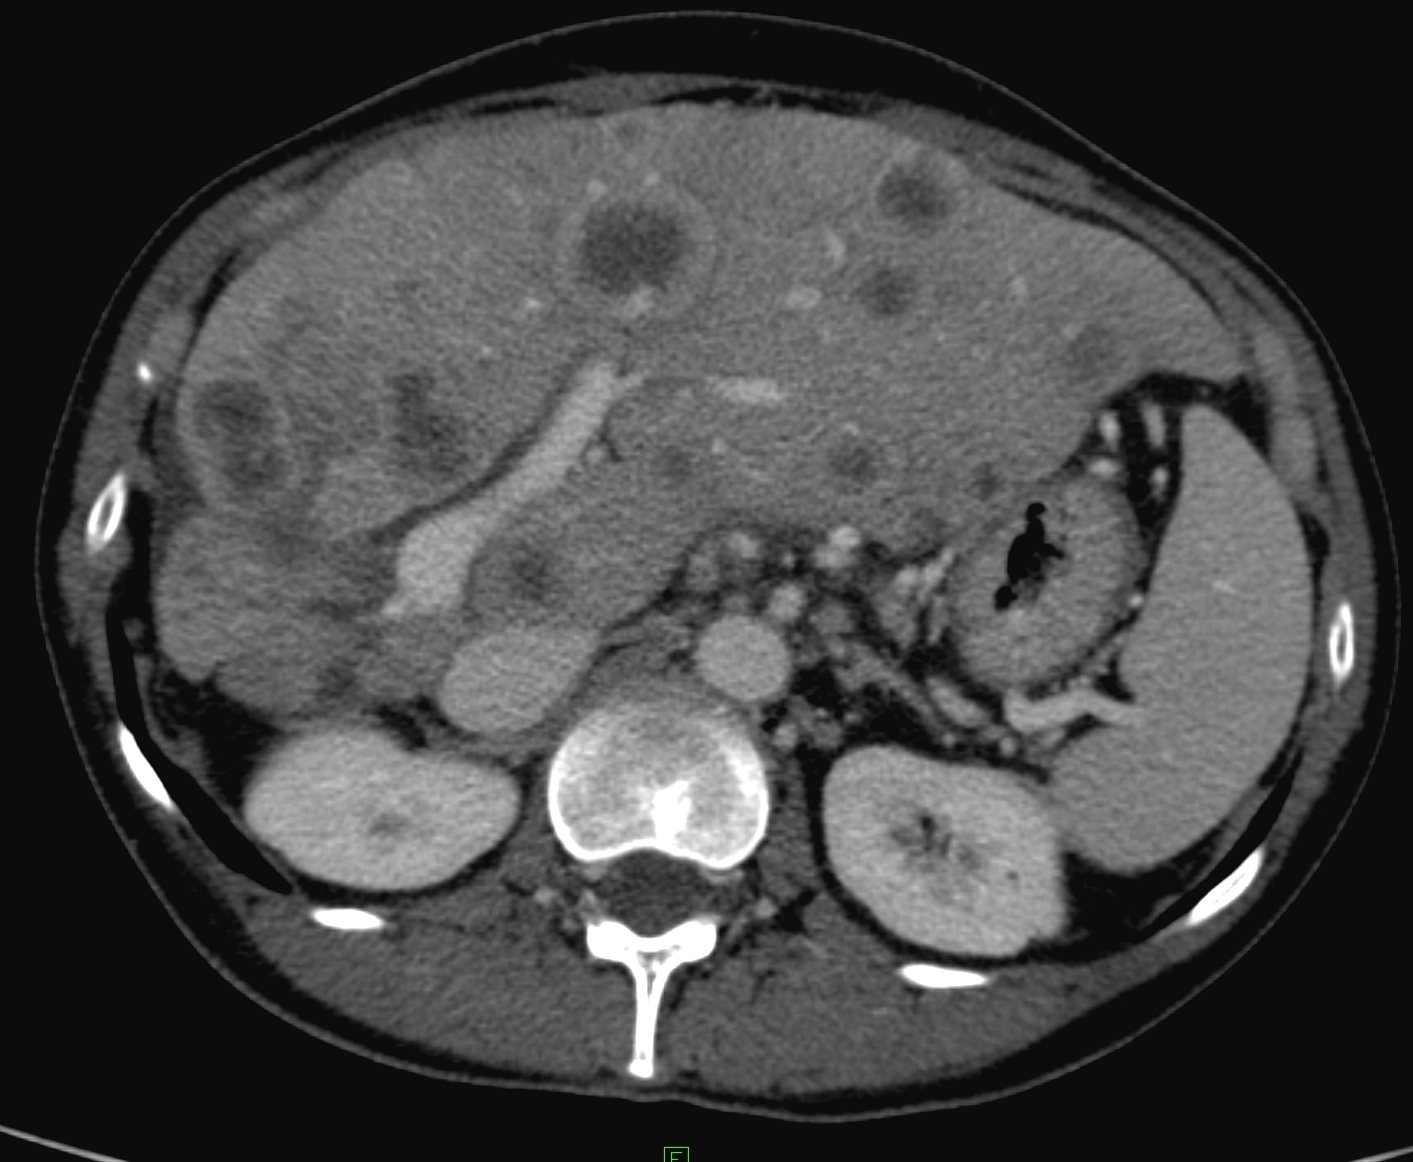

The most common malignant intrahepatic lesions are the metastases of various origin.

In the oncologic praxis especially in case of a patient with known colorectal, neuroendocrin or breast cancers, focused ultrasound examination of the liver has a special importance during the checkups.

US appearence and detectibility of the liver metastases can be very variable depending on the primary tumor. Sensitivity ranges between 53% and 84% according to various large studies.

Figure 23: Metastases of breast cancer in the liver, contrast enhanced CT

The liver metastases of colorectal origin are usually characterised by a bit inhomogeneous hyperechoic structure sorrounded by a hypoechoic rim. (Figure 25)

Figure 25: Liver metastasis of rectal cancer, US

In the central area of bigger (4-6 cm in diameter) metastases necrosis can also develop as so called „target” form (or commonly called as bull’s eye sign).

In the oncological practise, the most often performed imaging modality is nowadays the CT which is appropriate for both searching of liver metastases and the follow-up of the treatment efficacy in case of known liver metastasis. The decreased or increased vascularisation of the metastases can be well documented by appropriately performed three-phase multidetector CT in case of the liver, even from the size of 4-5 mm in most of the cases.